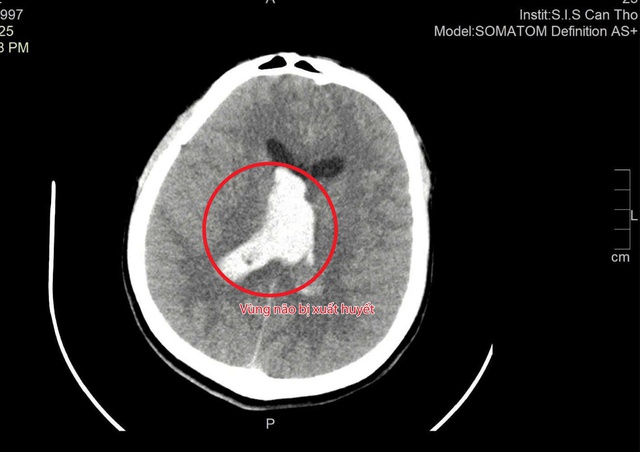

Trước đó, trong lúc nghỉ trưa, anh T. (28 tuổi, ngụ Cà Mau) đột ngột mệt, buồn nôn, co giật rồi rơi vào hôn mê sâu, phải đặt ống nội khí quản để thở. Ngay sau đó, anh T. được chuyển đến Bệnh viện đa khoa quốc tế S.I.S Cần Thơ. Kết quả chụp CT cho thấy anh bị xuất huyết não và não thất, kèm phù não nặng, nguy cơ tử vong rất cao.

Vùng não bị xuất huyết

ẢNH: BỆNH VIỆN CUNG CẤP